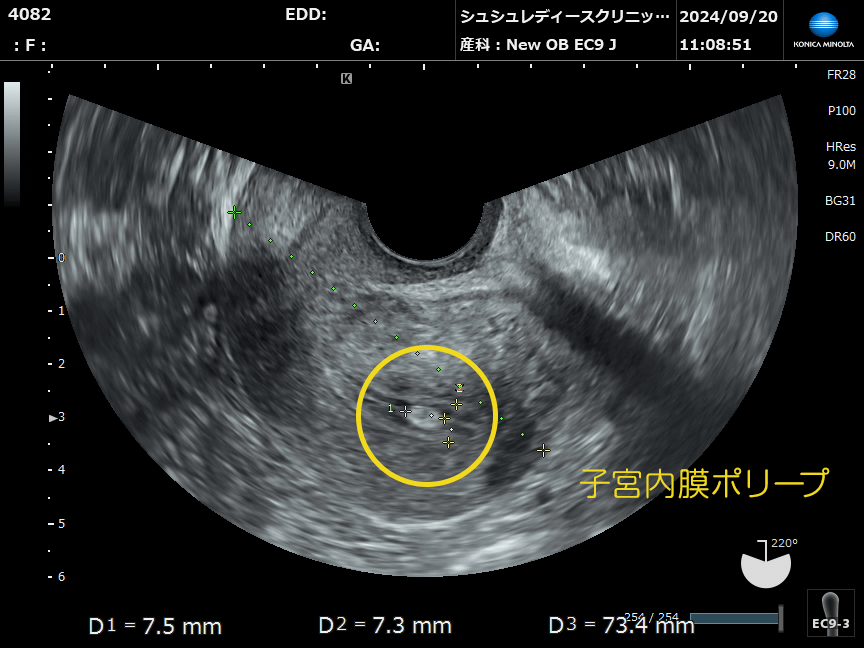

子宮内膜ポリープは、子宮の奥にある内膜の一部が増殖してできる柔らかいできものです。

大きさは数mm〜数cmまでさまざまで、1つの場合もあれば複数できることもあります。

多くは超音波(エコー)検査で発見されます。